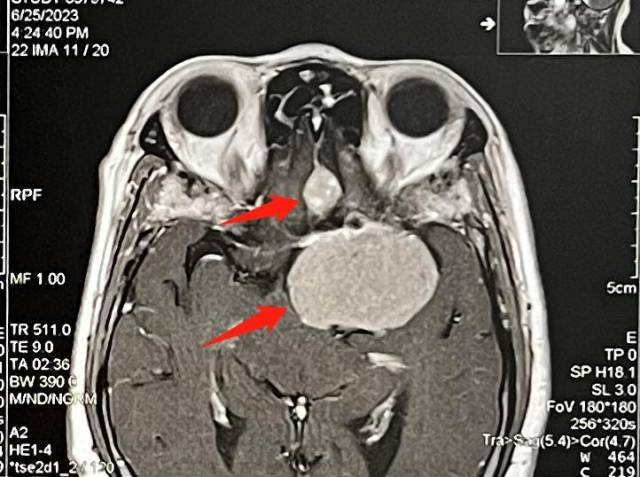

为寻求进一步诊疗,家人陪同秀姨来到广东三九脑科医院。该院神经外三科主任金鑫接诊后,查体发现患者左眼视力4.2、视野缺失。头颅核磁共振检查提示,其颅内左侧床突旁及左侧嗅沟各存在一占位性病变。

术前影像提示:左侧床突旁(下方)及左侧嗅沟(上方)占位性病变。 受访者供图

“患者脑袋里长了两个肿瘤,考虑是左侧床突旁的大肿瘤推压左侧视神经导致其左眼视力下降、视野变窄。位于左侧嗅沟较小的肿瘤虽还未引起症状,但任其生长,可导致嗅觉减退甚至丧失。”金鑫补充道。